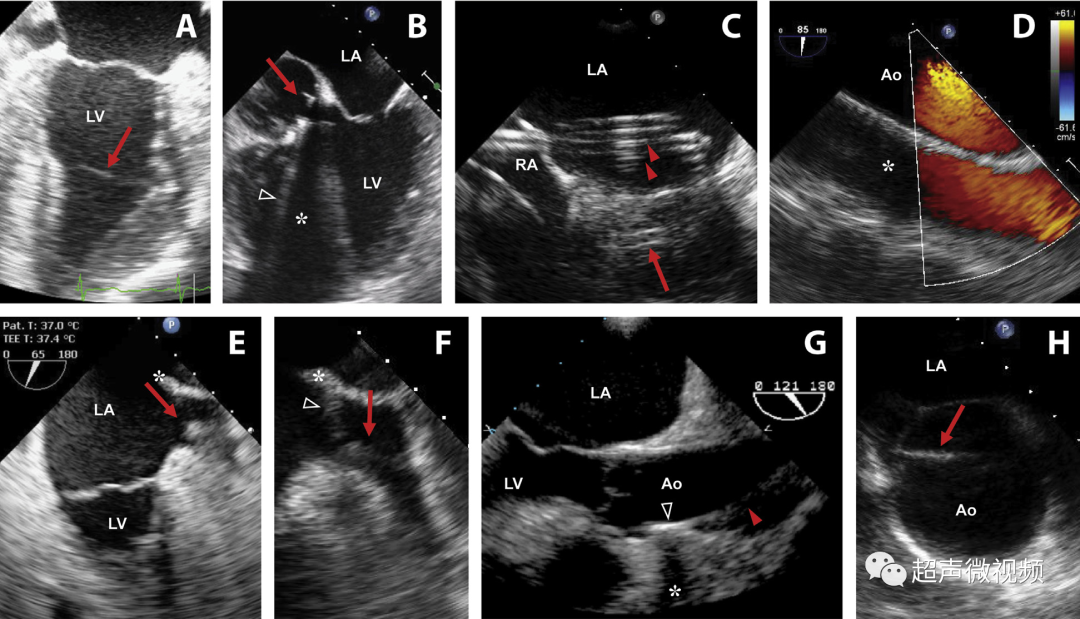

图10经食管图像伪影。

(A)二尖瓣小叶的混响伪影,距离探头正好两倍,表现为左心室腔内的导线(视频15)。

(B)机械主动脉瓣在右心室(RV)(星号)的大部分上投射声学阴影,并在侧面(箭头)投射混响(彗星尾)(视频16)。

(C)房间隔穿刺的导管,由于在(中空)导管上下侧的反射,出现一系列紧密间隔的混响(箭头),并且由于在探头本身的反射,在距离探头两倍的距离处出现一个混响。

(D)疑似两个平行的主动脉(Ao)的镜像伪影(星号)。注意血流也产生镜像伪像(视频17)。

(E)左心耳疑似血栓的混响伪影。从多个角度(见图F)进行分析证实存在华法林嵴的混响(星号),而不是真正的血栓(视频18-19)。

(G)在升主动脉(视频20)中延伸的钙化窦管连接(箭头)的旁瓣伪影(箭头)不应被误解为夹层。

(H)同样,升主动脉中的回声可能会被误解为夹层。